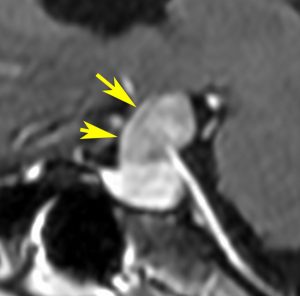

下垂体後葉腫瘍の典型的な画像です。下垂体柄(黄色の矢印)が伸びて前方へ偏移しています。またその直下に下垂体前葉(強い白の部分)がみえます。

ジャーミノーマでは下垂体柄も同時に太くなるのでジャーミノーマは否定的な所見です。

40代の女性に,軽度の両耳側半盲で発生したものです。視交叉と視床下部の下面に腫瘍があり,下垂体柄の位置が全くわからず,下垂体の前葉と後葉は侵されていません。ですから,下垂体柄から発生した腫瘍であり,pituicytomaが強く疑われます。T2ではほぼ等信号,小さなのう胞があり,ガドリニウムで強く増強されます。手術では正常下垂体柄の一部が右側にうすく残っており,幸運にも亜全摘出できて下垂体機能は温存できました。残存腫瘍は増大傾向を示していません。でも,このようなタイプを積極的に摘出すると,汎下垂体機能低下症を招くことが多いので,手術するかどうかの判断はとても難しいです。